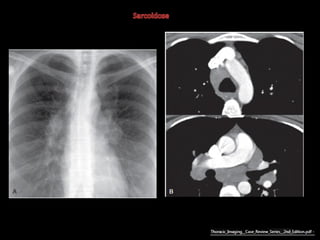

Sarcoidose

http://radiographics.rsna.org/content/30/7/1753.full.pdf+html